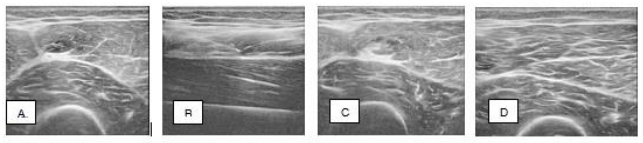

A 19-year-old female collegiate soccer player was evaluated for right thigh pain. While playing in a collegiate soccer summer league game, the patient sustained an acute injury to her right anterior thigh while kicking a soccer ball. She was unable to continue playing due to her pain. At presentation, the patient stated she has been playing soccer from a young age and had no history of prior injury to her right anterior thigh or lower extremity. She had previously consulted two Physical Therapists: one diagnosed her with a micro tear of the quadriceps tendon, while the other performed dry needling and cupping therapy for the right anterior thigh. The patient had not undergone a formal medical evaluation prior to presentation. On examination, the patient exhibited 4/5 weakness of the right thigh and tenderness in the right rectus femoris muscle. Nero vascular exam is found to be normal in both lower extremities and no other physical findings were observed. A diagnostic musculoskeletal ultrasound examination of the right complete thigh was performed the day of her initial visit to help determine the etiology of the patient’s pain and muscle. The diagnostic ultrasound showed an abnormal examination of the right thigh, consistent with a partial tear of the rectus femoris muscle belly (Figure 1)

At 6 weeks post procedure, the patient was pain free and completed her exercise program and returned to play soccer. She returned for an in-person reevaluation at 19 weeks post procedure. She remained pain free, exhibited normal strength during her physical exam, and a diagnostic musculoskeletal ultrasound of the right quadriceps was performed with evidence of a healed rectus femoris muscle (Figure 1).

Figure 1 Case 1: Ultrasound images of the right rectus femoris muscle partial tear injury, A. Pretreatment; B. and C. Time of treatment; D. 24 weeks post-treatment.